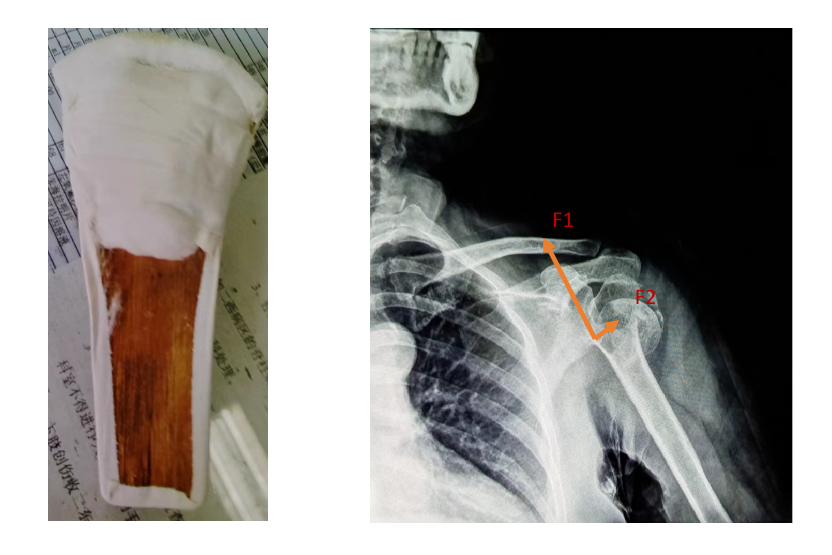

女,64岁,患肱骨近端粉碎性骨折10余天。骨折粉碎程度高,在躯干与肢干交界处的肱骨近端四部分骨折,成角角度约90度。

此时手法整复意义不大,又因家境困难,且患者本人惧怕手术,于是我们开启了医患焦虑的慢慢保守治疗之路,在“错位骨折如何得到最大化纠正”的力学固定上动足了脑筋。

第一部分的力由腋下处的夹板(笔者特别制作)提供的一个向上的力(F1),另一个则是支撑远端骨折的垂直肱骨干向上的力(F2)。

第二部分的力在断端下缘处额外增加一个小树皮,使之有一个向上的托举力(F3)。

第三部分的力通过“胶布墙”制造的牵拉力nF4,力的方向指向颈肩部方向。这个力至关重要,假如一条胶布的牵拉力是100克,那么20条胶布组成的“胶布墙”就有2000g了。

第四部分的力F5。肘与前臂夹角110°左右悬挂,使得肱骨干重力在肱骨干上的分力(mg余弦∠身体与上臂之夹角)较大,同时使在断端嵌插处得到牵拉修复的空隙。

诸力使得近断端沿肱骨干向上,远断端沿着肱骨干向下,骨折修复因子在这样的力学系中进行着正相“光合作用”——即成骨细胞、破骨细胞沿力学方向进行最大化的修复与重建。

采用此方法固定两月半,再拆除夹板外固定一个月后,在这四部分力的作用下,患者肱骨近端四部分骨折基本愈合,骨折成角90度在沿着其力的方向上得到最大纠正,患者已可以在家里骑三轮车干活。本次治疗共计花费约数千元。